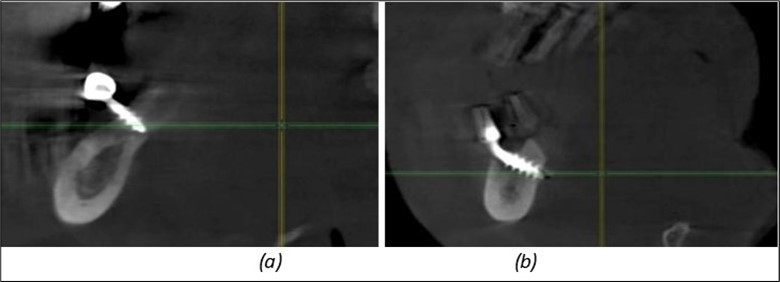

Figure 12.Implants fixed distally in quadrant 4 with fixation at the level of the mylohyoid line: (a) The most distal implant fixed in unaffected bone from the previous restoration; (b) The implant fixed in the area where the two stage implant was removed.

Figure 13.Corticobasal BCS implants fixed between the vestibular and lingual cortices with support on the basal bone: (a) BCS fixed between the lateral cortices; (b) BCS implant with support on the basal cortex.